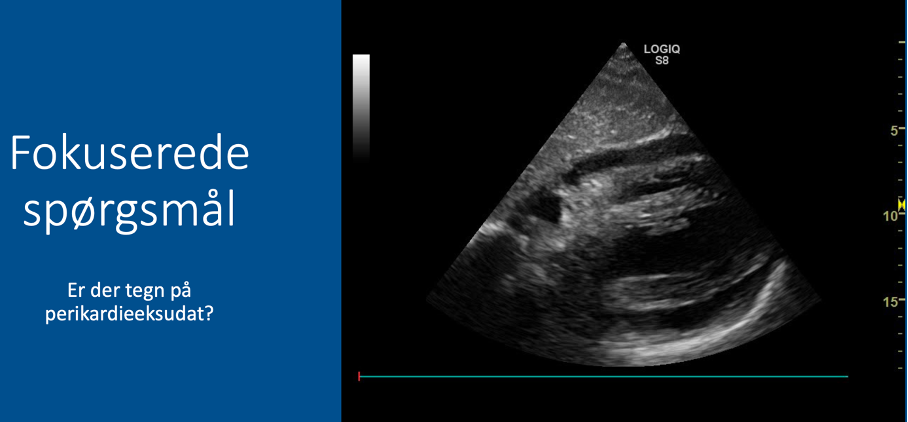

Fokuserede spørgsmål (FHUS):

* Perikardieeffusion: ja/nej?

Q